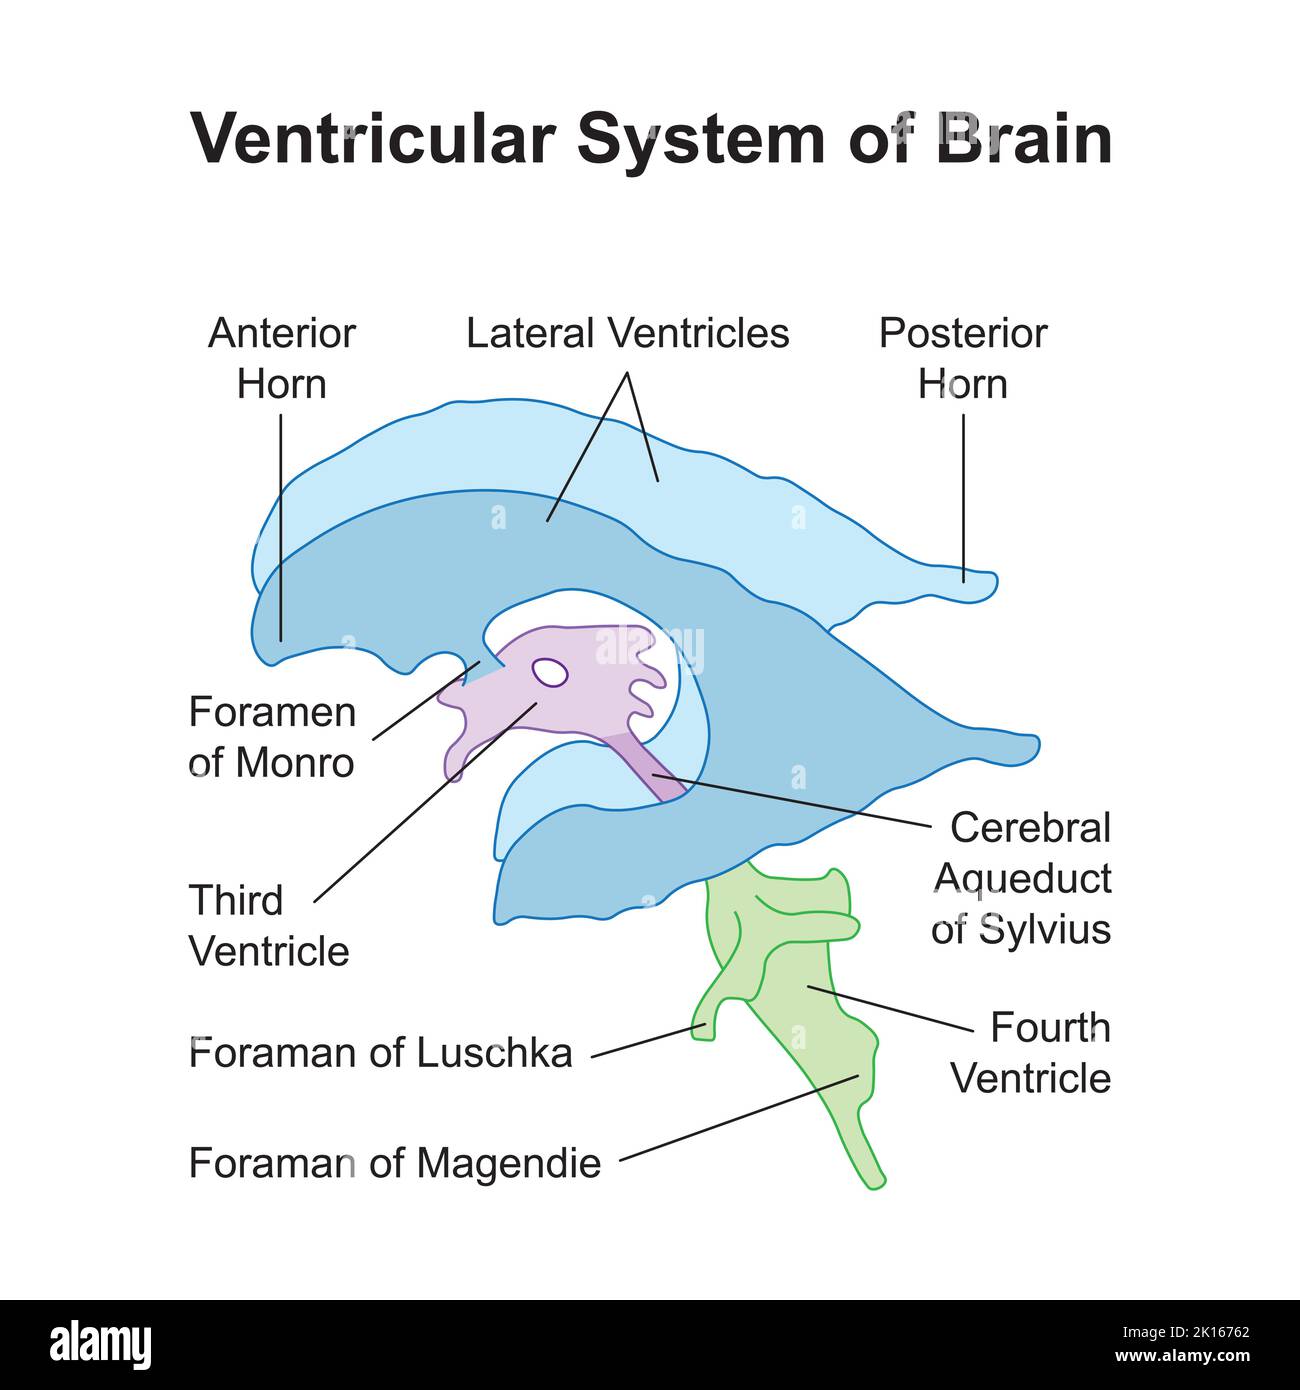

RM2AWF8JC–Die Anatomie des Nervensystems, vom Standpunkt der Entwicklung und Funktion. -Ant. HornCentra, Teil Latcral vnnInf. Horn Q virale Pari Ant. Horn. Ventrikel Ventrikel Ventrikel Ventrikel Ventrikel Ventrikel Ventrikel Ventrikel Ventrikel Ventrikel Ventrikel Ventrikel Ventrikel Ventrikel Ventrikel Ventrikel Ventrikel Ventrikel Ventrikel Ventrikel ^^ 176.-Zwei Ansichten der Hirnventrikel des Menschen: A, Dorsale Ansicht; B, laterale Ansicht. Das Vorderhorn oder Cornu anterius ist der Teil, der rostral zum interventrikulären Foramen liegt. Seine Dach- und Rostrallgrenze wird von Thecorpus callosum gebildet. Sein mediales

RM2AWFNN9–Menschliche Anatomie, einschließlich Struktur und Entwicklung und praktische Überlegungen d in einem sagittalen mesialen Abschnitt (Abb. 910) wird jede dieser Teilungen als mit einem Teil des Systems der Kommunikation von Räumen verwandt angesehen, die als die dritten Ventrikel des Lateralands, der Aquädukt von Sylvius und der vierte Ventrikel die oben genannten Gehirnhemisphären ausdehnen. Durch den Hirnstamm und unter dem Kleinhirn bis zum zentralen Kanal des Rückenmarks. Da die lateralen Ventrikel zwei innumerieren, ist die Theirstellung im Zusammenhang mit den Gehirnhemisphären, in denen sie liegen, lateral zum m

RM2AN4TWY–Handbuch der allgemeinen, beschreibenden und pathologische Anatomie (Band 2). Ventrikel, ein. Ventrikel des Kleinhirns, b. Aquädukt von Sylvius, C. Dritten Ventrikel, d. Lateralen Ventrikel, 1. Vordere Horn, 2. Hintere Horn, 3. Absteigend Horn, II. Textur, III. Gewicht, IV. Konsistenz, Kap. Iii. Umhüllt des Gehirns. Abt. Ich. Pia - mater, I. des Rückenmarks, II. Von Hirn, ein. - Externe Pia mater, b. Interne pia-mater, ich. Choroid Plexus des vierten Ventrikel, ii. Choroid Plexus des Großhirns, Art.ii.Apert-syndrom Membran, Art. hi. Dura-mater, I. spinalen Dura-mater, II. Zerebrale Dura-mater